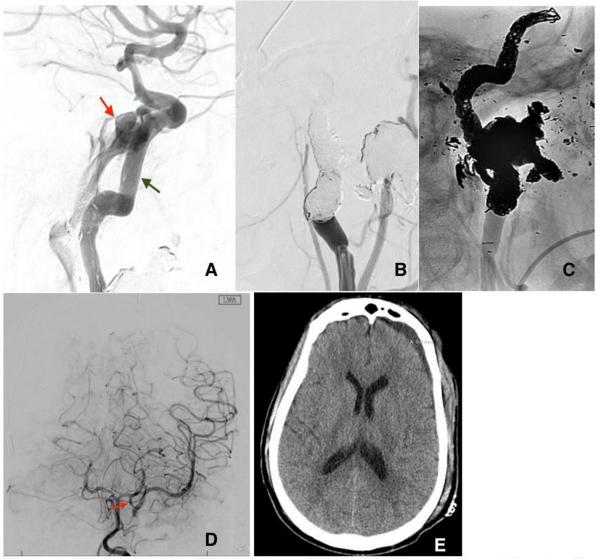

患者后来出现脑脊液漏,需要进行广泛的手术修复。为了寻找避免双重抗血小板治疗的治疗方法,决定重复BTO,为tCCF部位可能的左颈内动脉损伤做准备。患者通过BTO,左侧ICA从远端的海绵状节段成功栓塞到近端的远端颈部节段,没有任何流入颈动脉海绵状瘘的迹象(图4A~C)。停用双重抗血小板治疗,患者继续服用低剂量阿司匹林。面部骨折和脑脊液泄漏得到修复。患者的住院时间为27天,出院后转至康复机构,无左脑缺损(图4D、E)。出院时GOSE为5。

图4. (A)假性动脉瘤破裂部位的分流支架术后瘘管复发(红色箭头)。由于CCF的高流量,先前部署的支架(绿色箭头)错位。通过螺旋法对牺牲后左侧ICA进行了减影(B)和未减影(C)。(D)左颈内动脉牺牲后左椎动脉的脑血管造影AP视图,显示通过大的左后交通动脉(红色箭头)流入左大脑中动脉。(E)出院前头部CT显示左脑无缺血性改变的残余硬膜下血肿